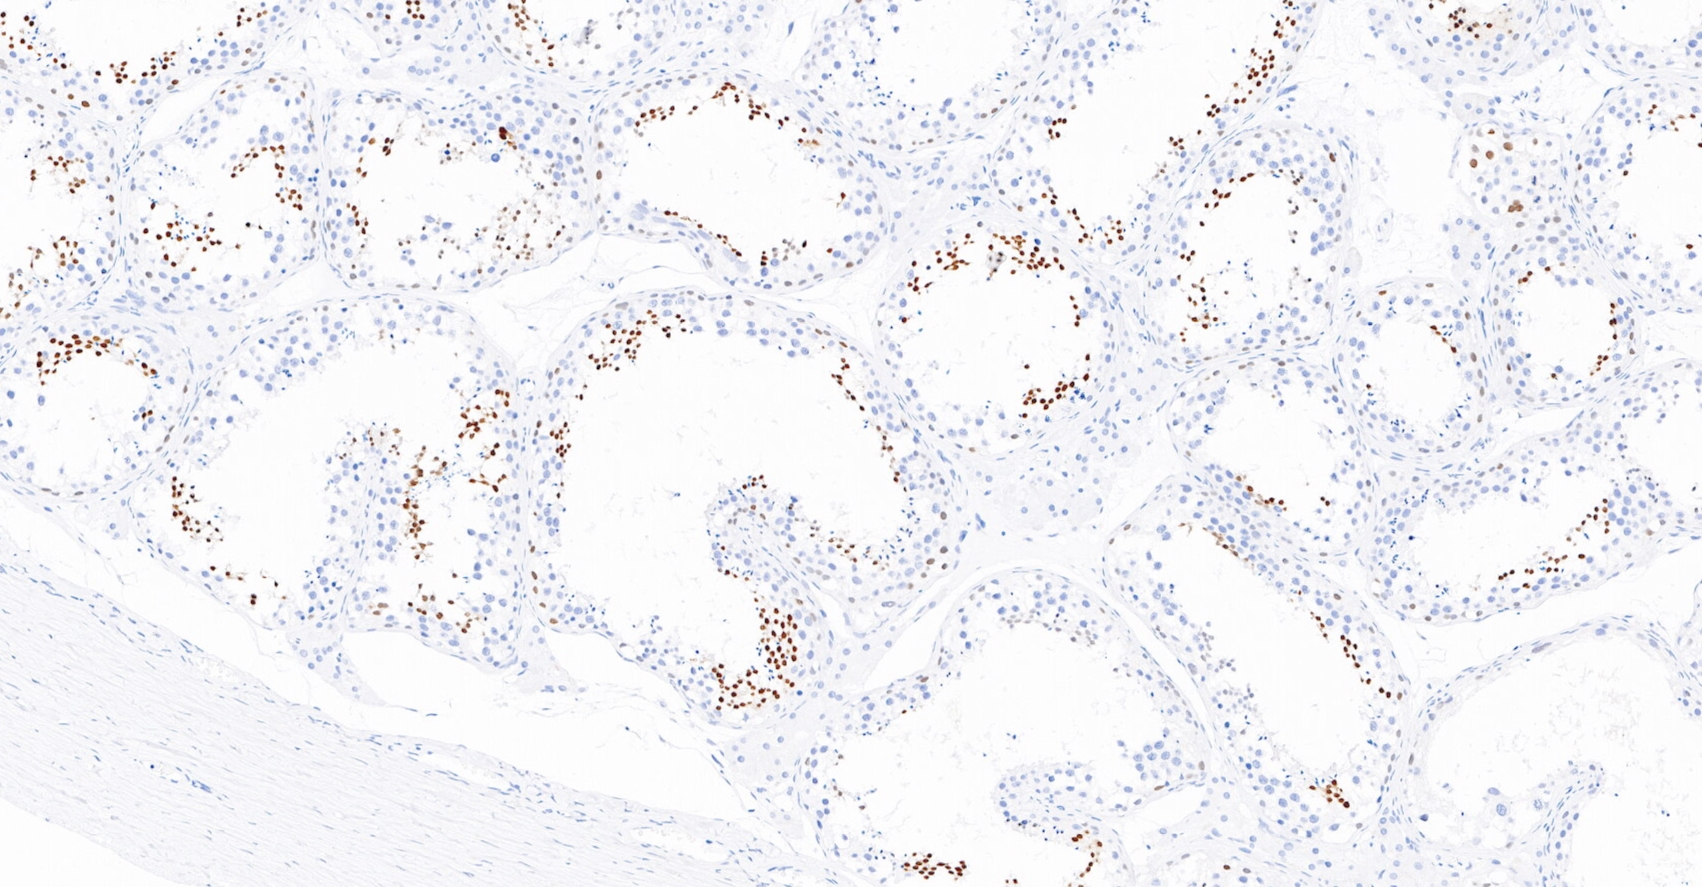

NUT为睾丸核蛋白,基因位于15q14,正常表达于睾丸和卵巢的生殖细胞。NUT中线癌是一种侵袭性肿瘤,伴有NUT基因相关性易位。因此,该抗体在NUT中线癌中有超过90%的核呈斑点状染色,主要用于NUT中线癌的诊断与鉴别诊断。

睾丸癌石蜡组织,用NUT染色,DAB显色